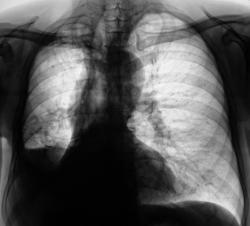

Двустороняя нижнедолевая плевропневмония (возможно застойного генеза), формирующееся левосторонее паракостальное осумкование.

Субтотальное снижение прозрачности левого легочного поля без смещения средостения.

Субтотальное снижение прозрачности левого легочного поля со смещением средостения вправо.